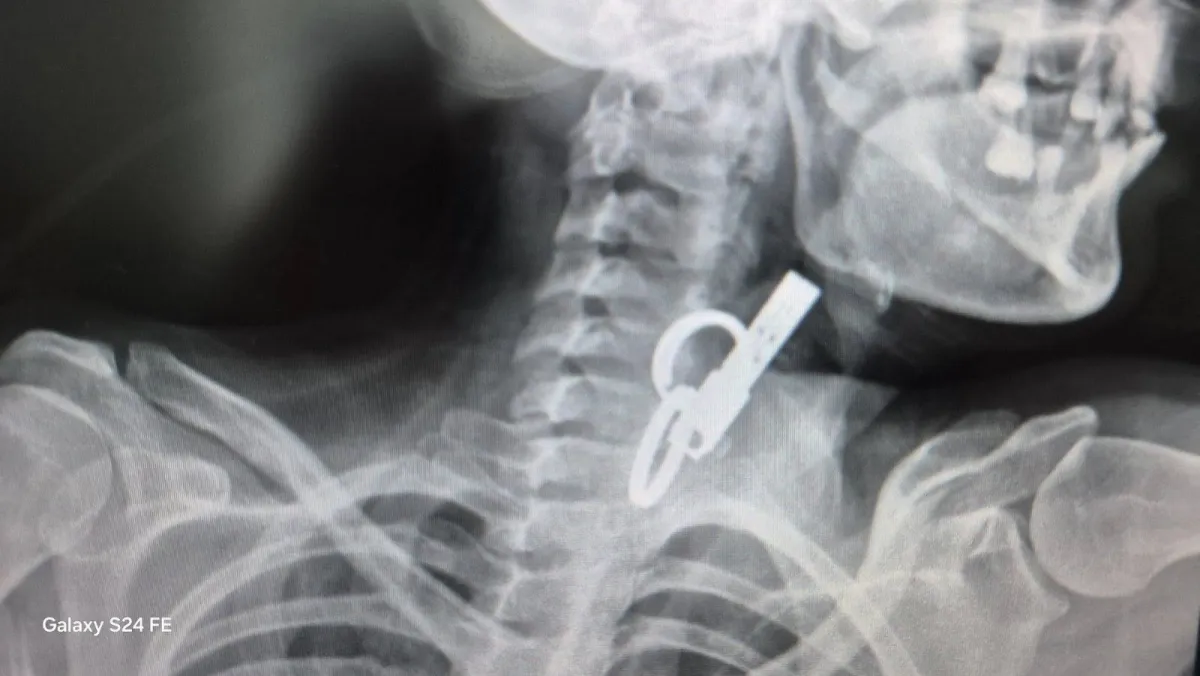

Стороннє тіло на знімку. Фото: Facebook Гусятинської комунальної лікарні

На Тернопільщині лікарі КНП «Гусятинська комунальна лікарня» цілодобово надають допомогу та провели унікальне ендоскопічне втручання, діставши ключі зі стравоходу без операції.

У КНП «Гусятинська комунальна лікарня» жінці терміново надали допомогу після того, як у її стравоході застрягли ключі з кільцями. Лікарі цілодобово чергової служби провели ендоскопічне втручання без операції та розрізів. Про випадок повідомили на сторінці Facebook медзакладу.

«Завдяки наявності сучасного ендоскопічного обладнання та злагодженій роботі команди фахівців у закладі успішно проведено ендоскопічне видалення великого стороннього тіла», — йдеться у повідомленні лікарні.

Після процедури стан пацієнтки був стабільний. Самопочуття лікарі оцінили як задовільне. Жінка не потребувала відкритого хірургічного втручання. Ключі мали металеві кільця, що значно ускладнювало втручання та створювало ризик травмування стравоходу.

Сторонній предмет на знімку. Фото: Facebook Гусятинської комунальної лікарні